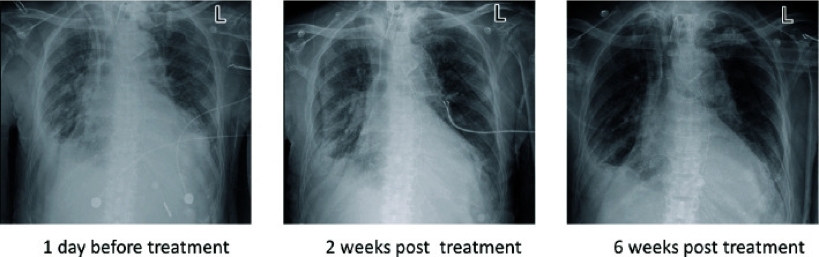

中国科学院深圳先进技术研究院马迎飞研究团队用噬菌体为患者治疗,随着治疗的进行,患者病情逐渐好转,肺部的耐药细菌也检测不到了,X光片下早已经苍白的肺部也逐渐转为了坚实的黑色。

X光下病人的肺部从肺炎症状的白色逐渐转化为健康的黑色图片来源:论文作者供图)